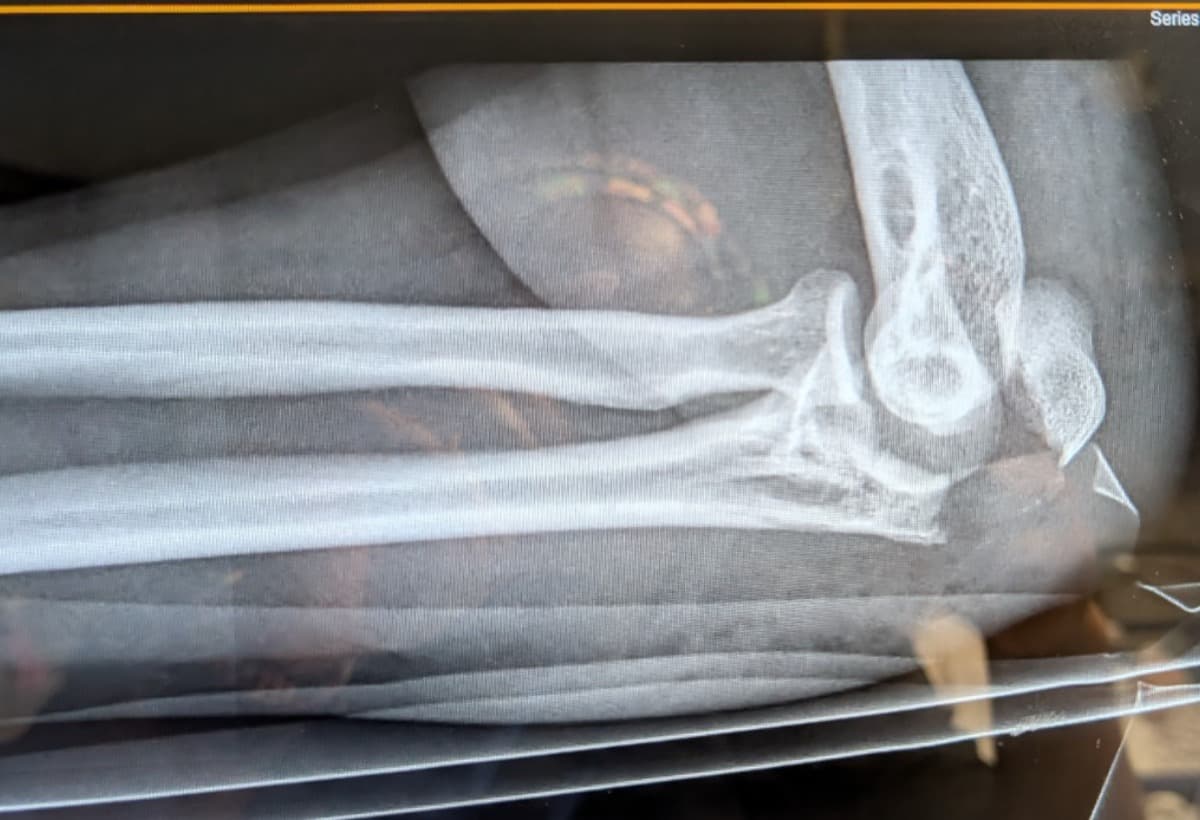

My shattered elbow